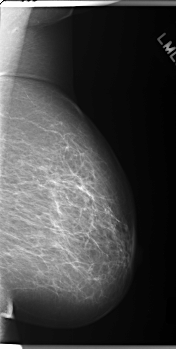

C_0159_1.LEFT_MLO

LEFT_MLO LINES 5920 PIXELS_PER_LINE 2992 BITS_PER_PIXEL 12 RESOLUTION 50 NON_OVERLAY